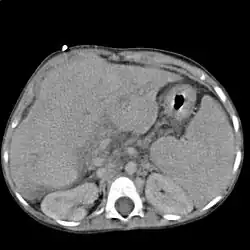

widok w przekroju poprzecznym

Zdiagnozowanie zwłóknienia wątroby odbywa się na podstawie objawów, wywiadu i oceny historii chorób pacjenta, badania fizykalnego i badań laboratoryjnych. Jeśli podczas badania okaże się, że wątroba jest twarda i powiększona, zwykle zarządza się badanie krwi.

Badania instrumentalne umożliwiające obejrzenie i oszacowanie rozmiarów uszkodzeń to: komputerowa tomografia osiowa (CAT), ultradźwięki, rezonans magnetyczny, badanie z użyciem radioizotopów.